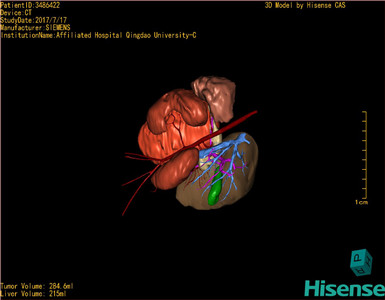

肾母细胞瘤-CH-001-N-001503

CT结果输入海信CAS系统后行3D重建及手术规划后,于2017-7-21全麻下行“左肾切除术”手术治疗:

术前三维重建及手术方案设计:

将0.625mm双源薄层CT资料的静脉期和动脉期Dicom格式文件导入海信CAS系统。

通过调节窗宽窗位调整CT序号,对肿瘤,肝实质,胆囊,下腔静脉,肿瘤,肝动脉、门静脉及肝静脉等进行三维重建;系统自动计算肿瘤体积和肝脏体积。

模拟手术操作,自动计算切除肿瘤体积。肝脏体积为215ml,肾脏肿瘤大小为284.6ml通过术前模拟手术,精准判断手术可行性。

术前三维重建:

重建图片